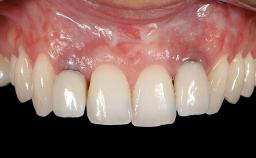

Early Implant Placement, Contour Augmentation, and Autologous Connective-Tissue Graft Using a Tunneling Technique to Replace an Upper Incisor with Generalized Gingival Recession

Variations in soft-tissue volume, evidenced either by an overabundance (Evian and coworkers 1993; Levine and McGuire1997; Dolt and Robbins 1997) or by a deficiency of soft or hard tissue can complicate implant-supported rehabilitations in the esthetic zone (Lorenzana 2008; Lorenzana and coworkers 2009). The present case illustrates the replacement of a failing upper left lateral incisor complicated by generalized severe gingival recession in the esthetic zone.

| Soft Tissue Contour and Volume | Significantly deficient |